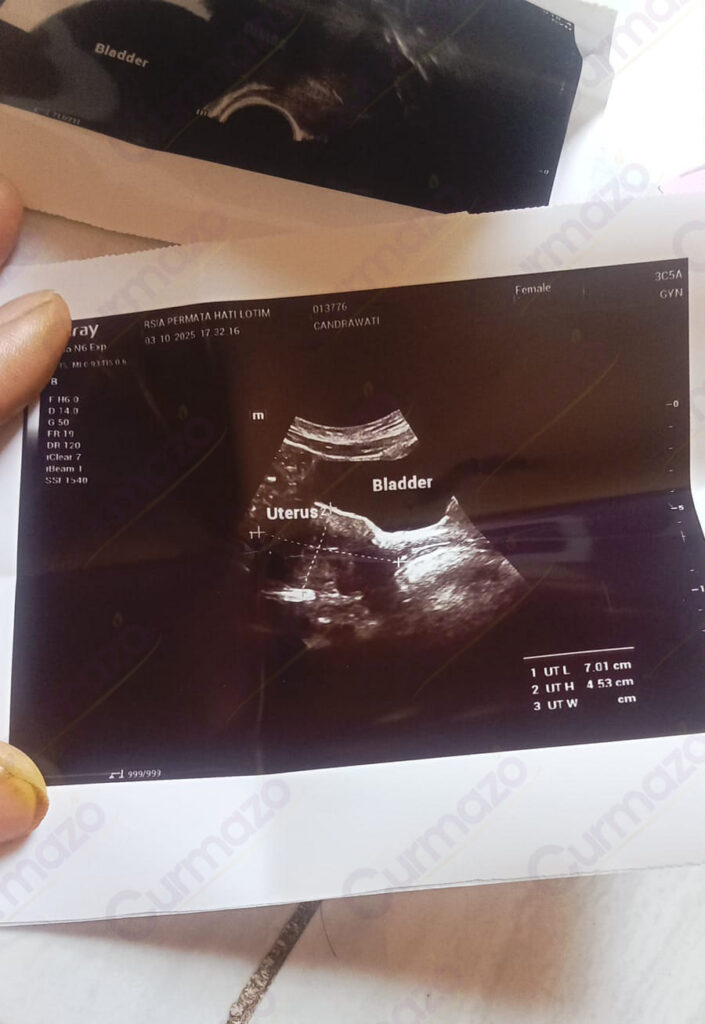

Tanggal 5 Oktober 2025 saya USG di dokter yang sama, dokter kaget lihat kista saya sudah tidak ada. Sebelumnya saya juga tidak menyangka kalau hilang total, pikir saya kalo mengecil aja udah alhamdulillah banget tapi justru hilang total. Dokter juga gak nyangka, akhirnya USG lagi sampai 3 kali. Namun, hasilnya tetap sama saja 3 kista sudah tidak ada yang berarti hilang total!

Foto hasil USG after: